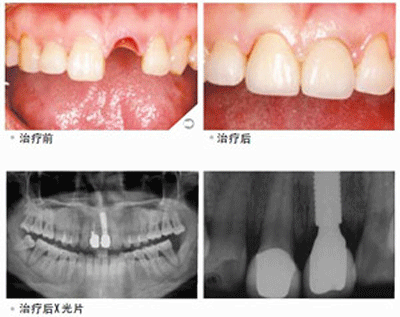

想要具体了解牙齿缺失福州哪家医院好 点击【在线咨询】直接问医生!方便!快捷!牙齿缺失在目前修复方式使种植牙,使用时间久,稳固耐用,而且舒适美观,而且还能即拔即中,即种即用。种植牙这样的特点大大的方便了人们的生活。但在医院选择方面却很为难,牙齿缺失福州哪家医院好?直接与医院在线医师一对一通话,方便!快捷!了解详情就医指导。

贝臣齿科率先引进微创术,国内医生级医生进行种植牙手术,利用手术方式来完成种植牙过程。与传统的种植牙相比,具有以下优势:

1.创伤小,微痛苦。仅有几毫米的微小切口,将人工牙根“种”入口腔内,摆脱了传统种植牙缝合、拆线等步骤,创伤小,术后即可进食,几乎微痛苦。

2.时间短,方便快捷。一般情况下,种植体植入手术只需要数十分钟即可以完成,大幅缩短拔牙后的等待时间,快速修复牙齿。

3.效果好,无副作用。由于选用的是与人体相容性较好的材料,种植牙对人体不会产生任何不良的副作用,对牙齿没有任何损伤,安全可靠。

4.稳固性好,舒适度强。人工牙根与牙槽骨紧密结合,就像真牙似的扎根在口腔里,因此具有很强的稳定性,而且无需卡环或牙套,所以口腔内没有异物感,非常舒适方便。